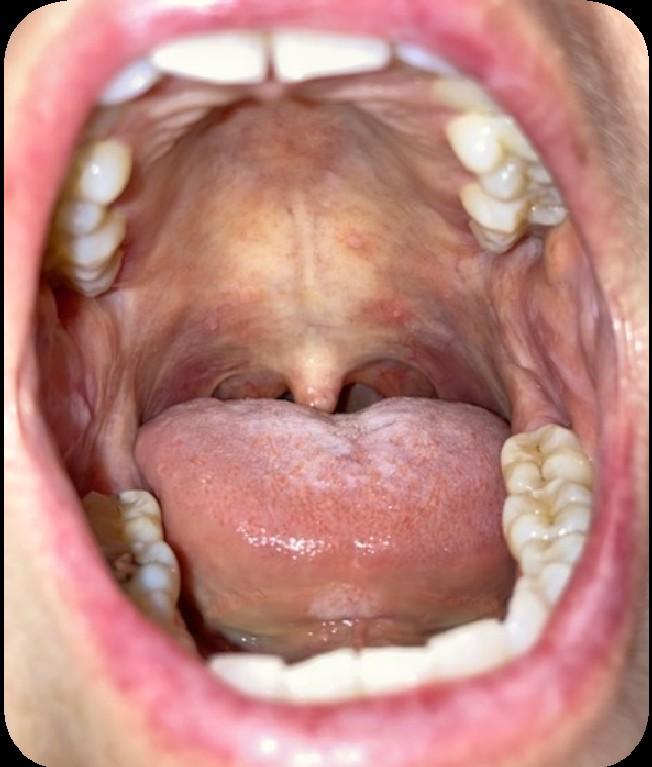

Oral GVHD

(Oral Graft vs. Host Disease)

Oral Graft vs. Host Disease

• Complication following allogeneic HSCT which results in mouth sores, mouth pain and sensitivity to normally tolerated foods and drinks, and reduced mouth opening.

• May also affect the salivary glands, resulting in dry mouth and/or the development of small blisters (superficial mucoceles) on the inside of the lips and the palate.

Oral Graft vs. Host Disease: Tips

• Avoid spicy and acidic foods

• there are no specific foods that actually make the condition get worse.

• Dry mouth may further worsen the condition

• For acute pain relief, topical anesthetic can be applied to the lesions.

• To reduce the inflammation, an antiinflammatory agent, such as a topical steroid can be used

• When using a steroid preparation, risk of developing an oral yeast infection is increased

• Oral cancer surveillance